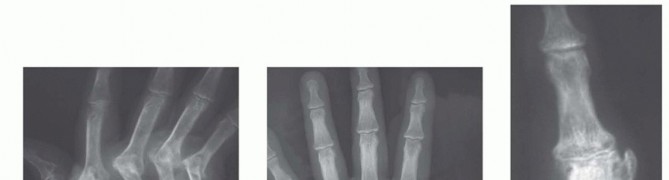

Proximal Interphalangeal and Metacarpophalangeal Joint Silicone Implant Arthroplasty